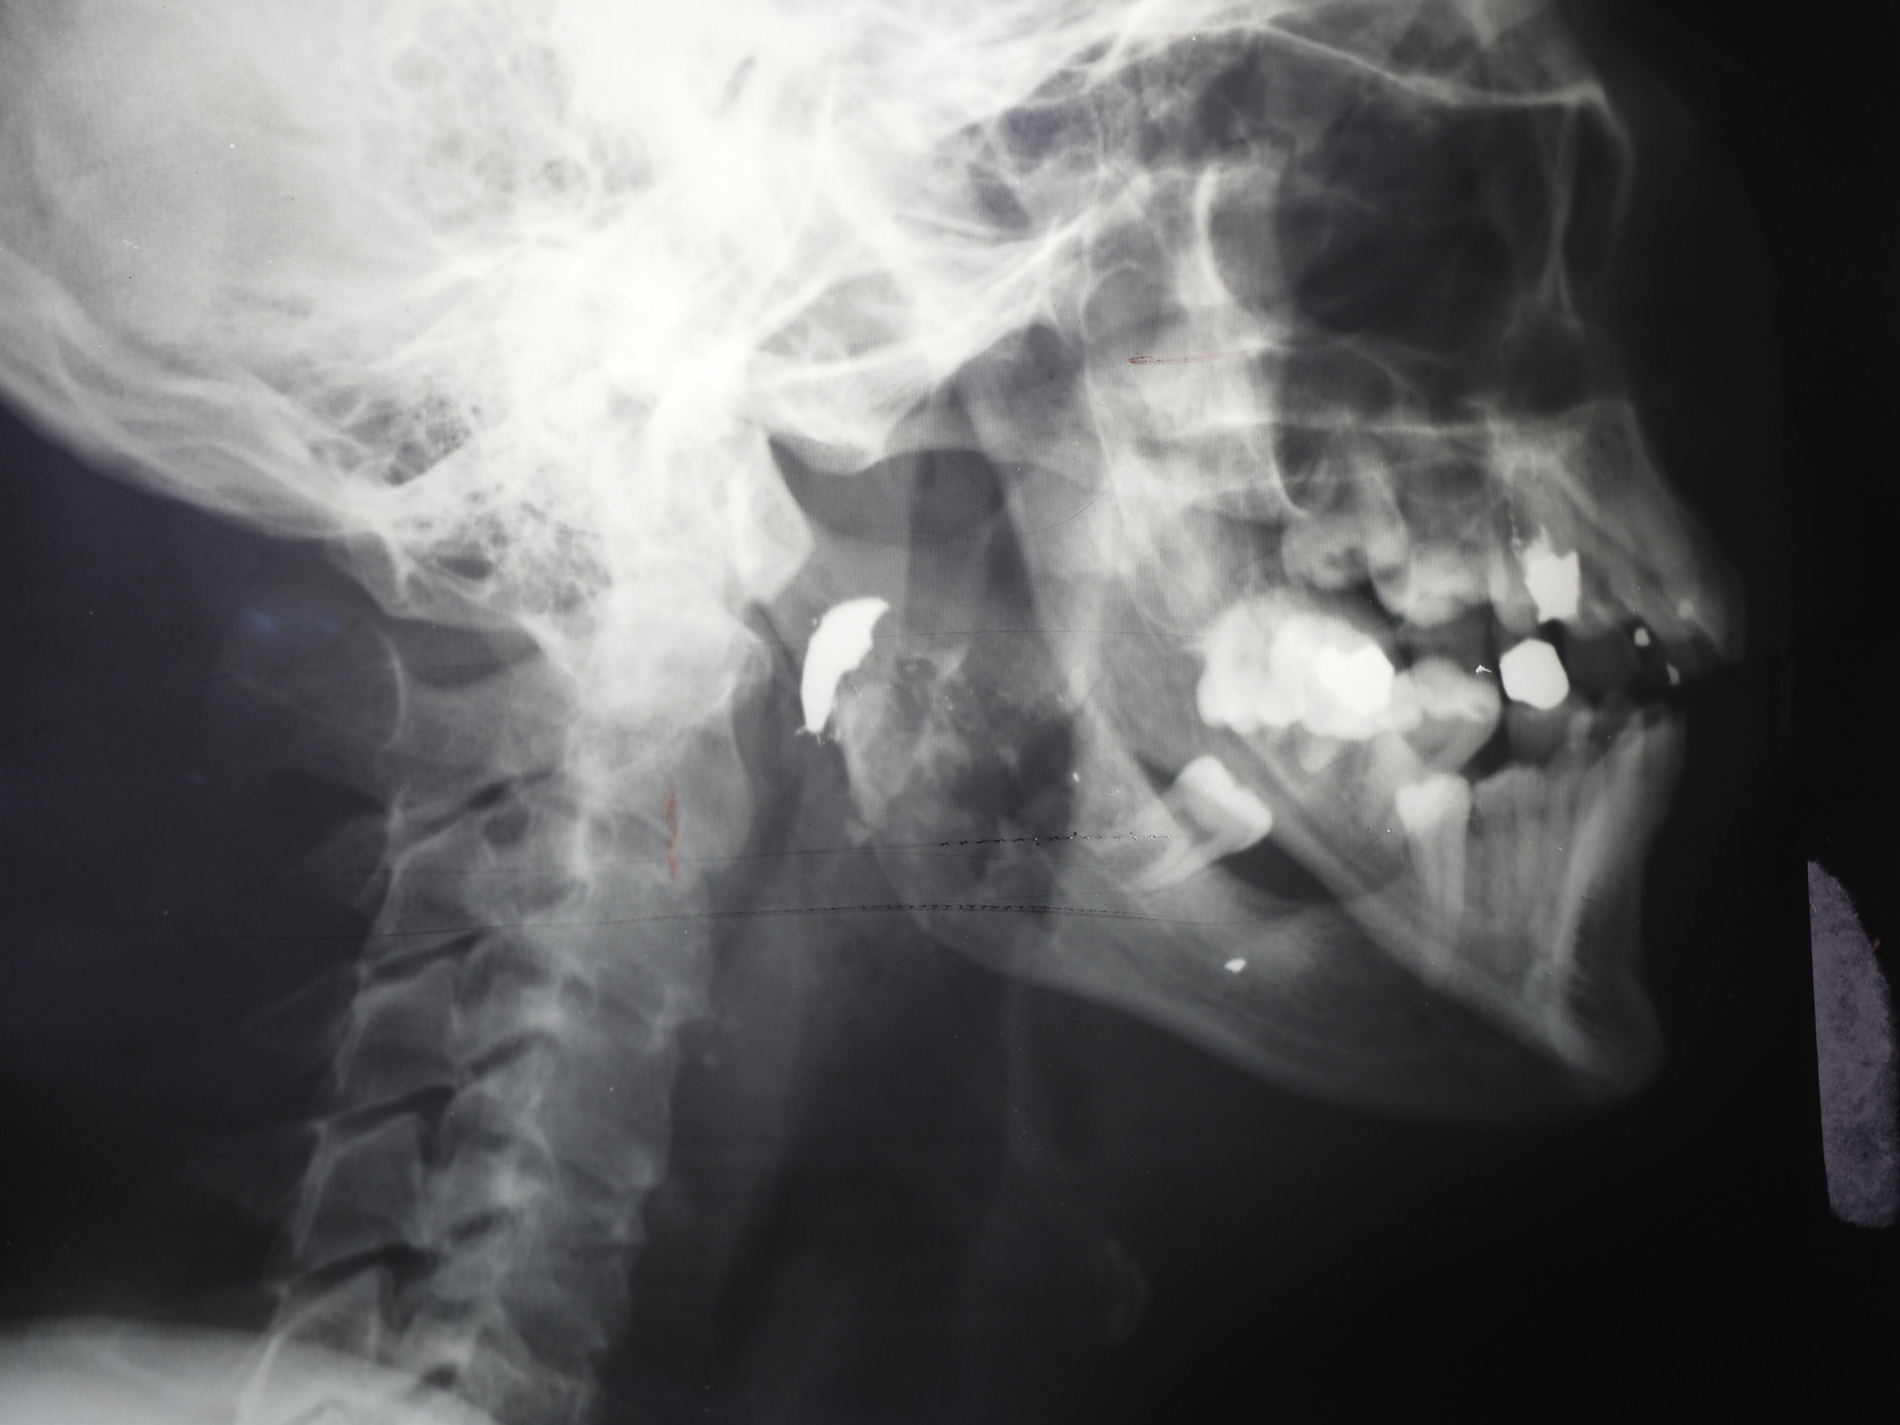

Alles scheint im Vorfeld generalstabsmäßig derart durchorganisiert gewesen zu sein, dass man vorbereitet war, mit Beginn des Krieges die verwundeten deutschen Soldaten systematisch zu erfassen. Patientenakte, klinische Bilder, Röntgenaufnahmen, Therapiemaßnahmen. Krankenblatt um Krankenblatt, alle datiert auf die ersten Septembertage, zieht Haesler aus der Kiste.

Darunter die Akte des hier abgebildeten, jungen Soldaten mit dem Einschussloch in der Wange – „vermutlich ein Durchschuss, bei dem die Kugel aus dem Mund wieder ausgetreten ist, weil sie röntgenologisch nicht zu orten ist“, sagt Haesler. Sukzessive dechiffriert man die Sütterlinschrift: „Krankheitsbezeichnung: Zertrümmerungsfraktur“, dann das Zugangsdatum „6.9.1939“.